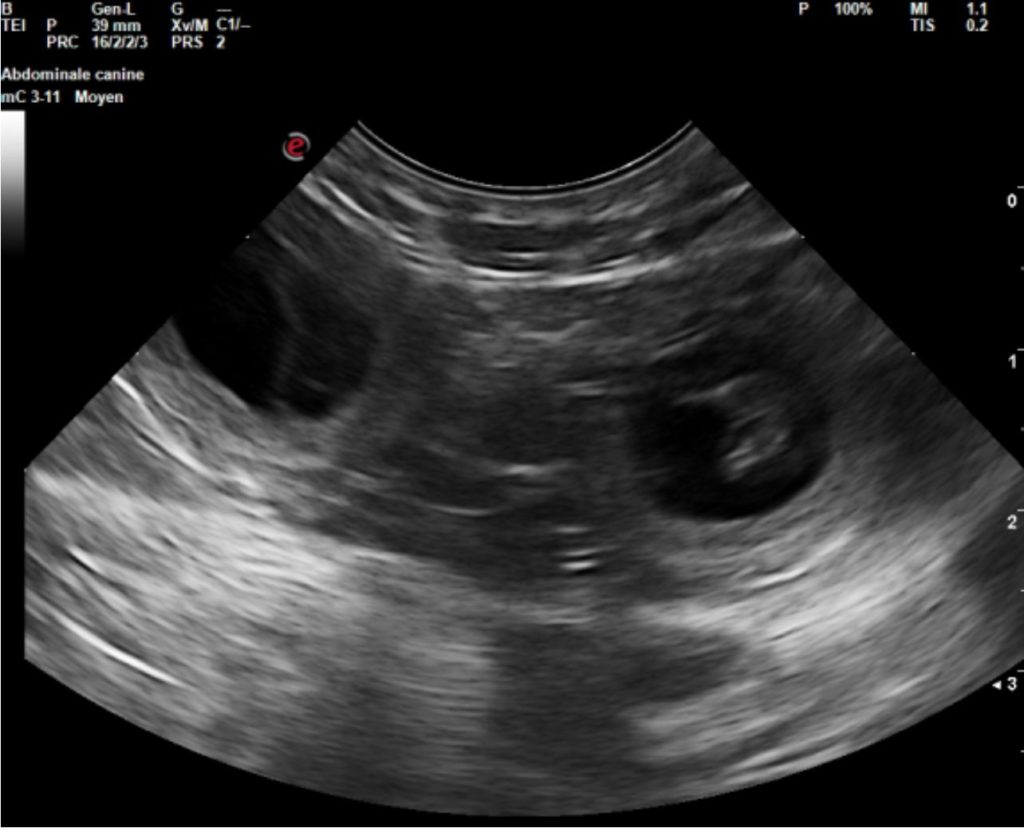

Portée G – Echographie

La gestation est confirmée.